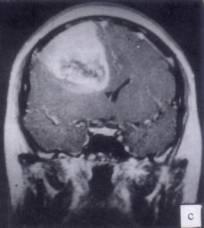

病历摘要:??患者男性,52岁。头痛伴呕吐2月,呕吐呈喷射性。既往身体健康。体检:神清,表情淡漠,反应迟钝,双眼底视神经乳头明显水肿,左鼻唇沟稍浅,左腹壁...

问题 病历摘要:??患者男性,52岁。头痛伴呕吐2月,呕吐呈喷射性。既往身体健康。体检:神清,表情淡漠,反应迟钝,双眼底视神经乳头明显水肿,左鼻唇沟稍浅,左腹壁反射减弱,左上下肢肌力4级,左Babinski征(-)。 下列关于脑叶切除术范围的叙述哪些是正确的?